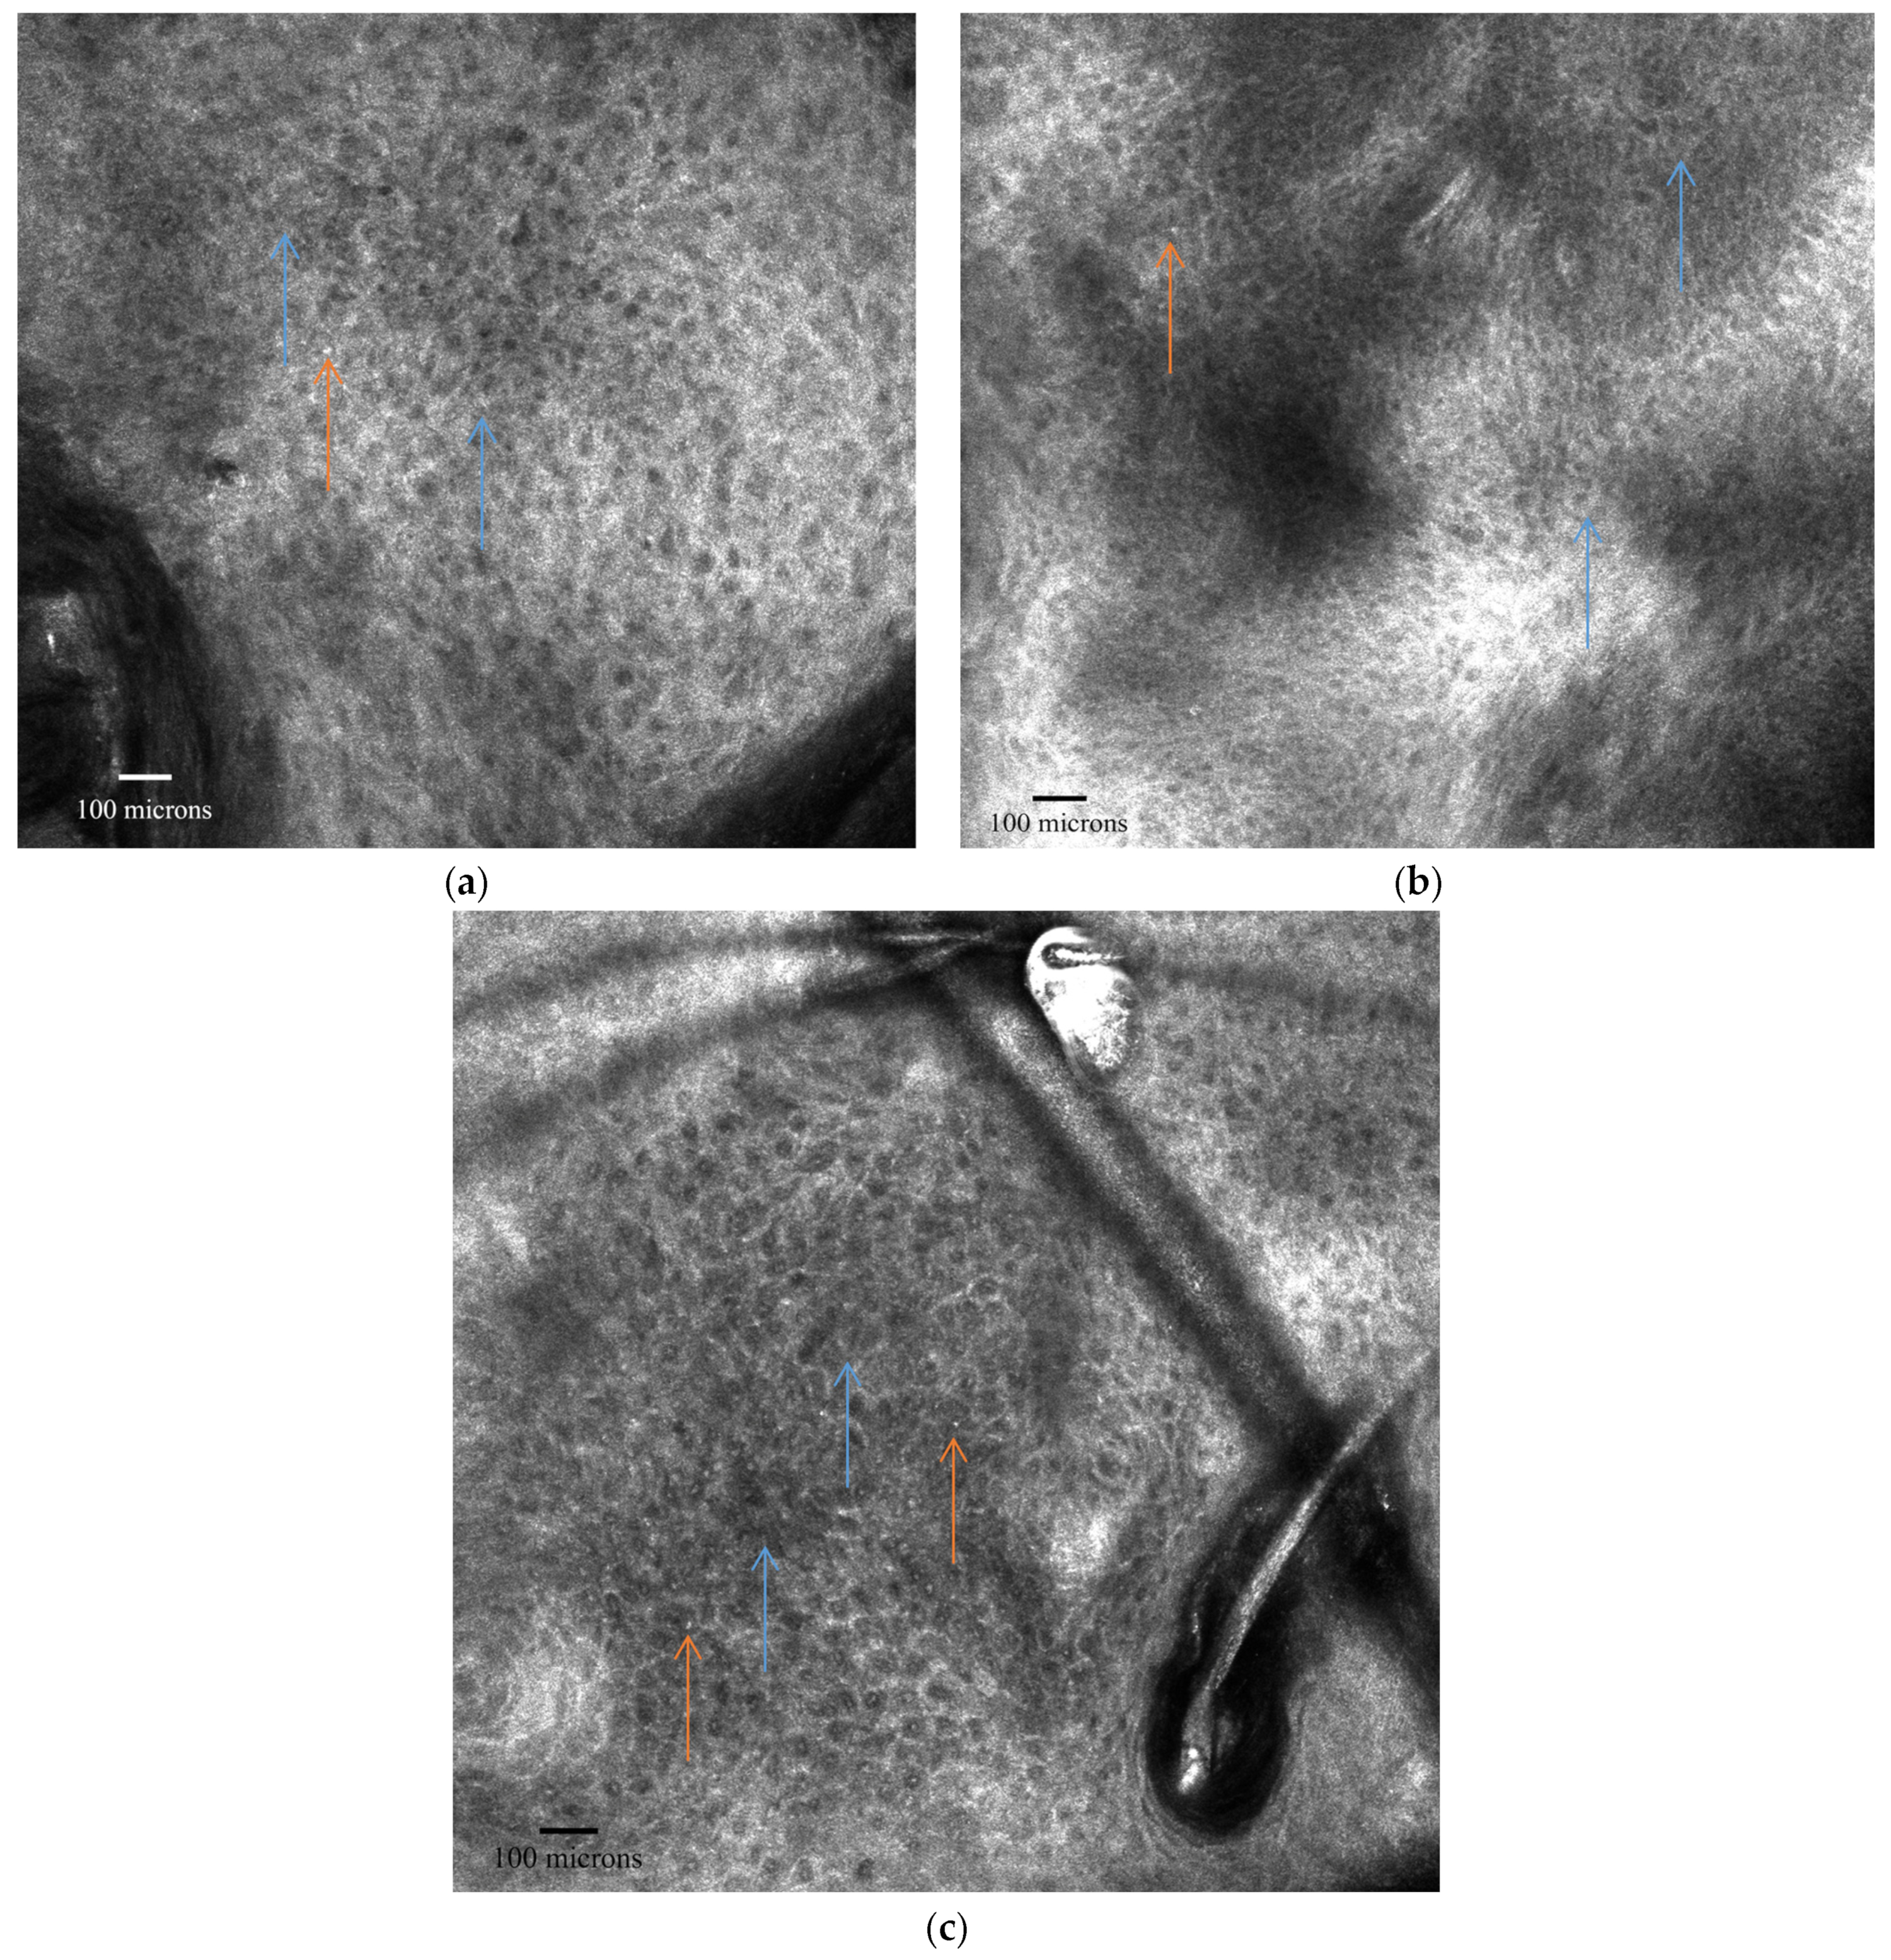

| Skin Layer | RCM Features of AK |

|---|---|

| Stratum Corneum | Superficial disruption with large single keratinocytes Nucleated cells (parakeratosis) Small bright cells with dark centers (neutrophils) |

| Stratum Granulosum/Spinosum | Atypical honeycomb pattern: variations in cell size and morphology Broadened honeycomb pattern: areas with broadened and blurred intercellular connections Loss of regular epidermal architecture |

| Dermis | Slightly dilated blood vessels Solar elastosis: moderately refractive lace-like material adjacent to collagen bundles |

| AK Grade | Description |

| Grade 1 | Focal areas of atypical, honeycombed pattern at the stratum spinosum level, mixed with areas of typical honeycombed pattern. |

| Grade 2 | Diffuse atypia of keratinocytes in both the stratum spinosum and granulosum, with marked variation in cell sizes and shapes. |

| Grade 3 | Markedly atypical, honeycombed pattern with partial disruption of normal epidermal layers (disarranged pattern), wide variability in keratinocyte size and shape, and irregular intercellular connections. |